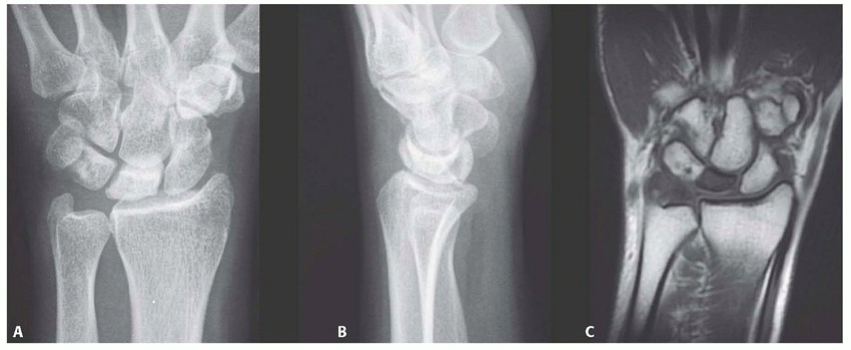

Vascularized Bone Grafting and Capitate Shortening Osteotomy for Treatment of Kienböck Disease

CAPITATE SHORTENING OSTEOTOMY